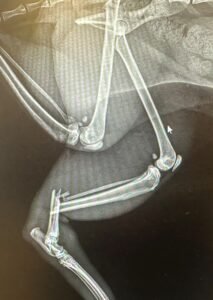

Digital X-rays – Radiographs (X-rays) are usually the diagnostic imaging administered to evaluate your pet. Our office utilizes digital X-rays because they are more accurate and display a higher contrast. Because of their accuracy, technicians are able to take fewer images resulting in less pet discomfort. Digital X-rays also project less radiation than traditional X-rays which improves safety for our staff.

The process for taking radiographs of your pet depends on their temperament and their underlying medical condition. For animals that are calm, we can generally take diagnostic images with minimal manual restraint. We prefer this method for animals that are critically ill and may not handle sedatives well. If your pet is more excitable or in pain, we will generally use sedation to help facilitate quality imaging. Pets must lay very still for the images to be of high quality, so in many cases sedation is necessary.